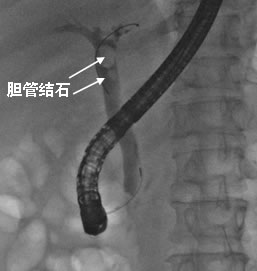

消化内科陈渭副主任医师仔细查看病人、综合分析病情,考虑患者反复腹痛为胆道结石所导致,而非胃炎,遂行ERCP治疗。术中造影证实胆总管内果然有多枚结石,最大达1.2X1.0cm,陈渭医师予内镜下全部取出,手术全过程仅用了20分钟,术后周先生腹痛即完全缓解,再没发作。

ERCP是经内镜逆行胰胆管造影术的英文缩写。十二指肠镜经口腔通过胃肠道到达胆、胰管与十二指肠的汇合口,插管进入胆、胰管并进行造影、切开、扩张、取石、置入支架等微创操作,是目前公认的诊断胆胰管疾病的金标准,也是胆胰疾病的重要微创治疗手段,为胆总管结石的首选治疗方式,尤其适合不能耐受或不愿行手术治疗的患者。